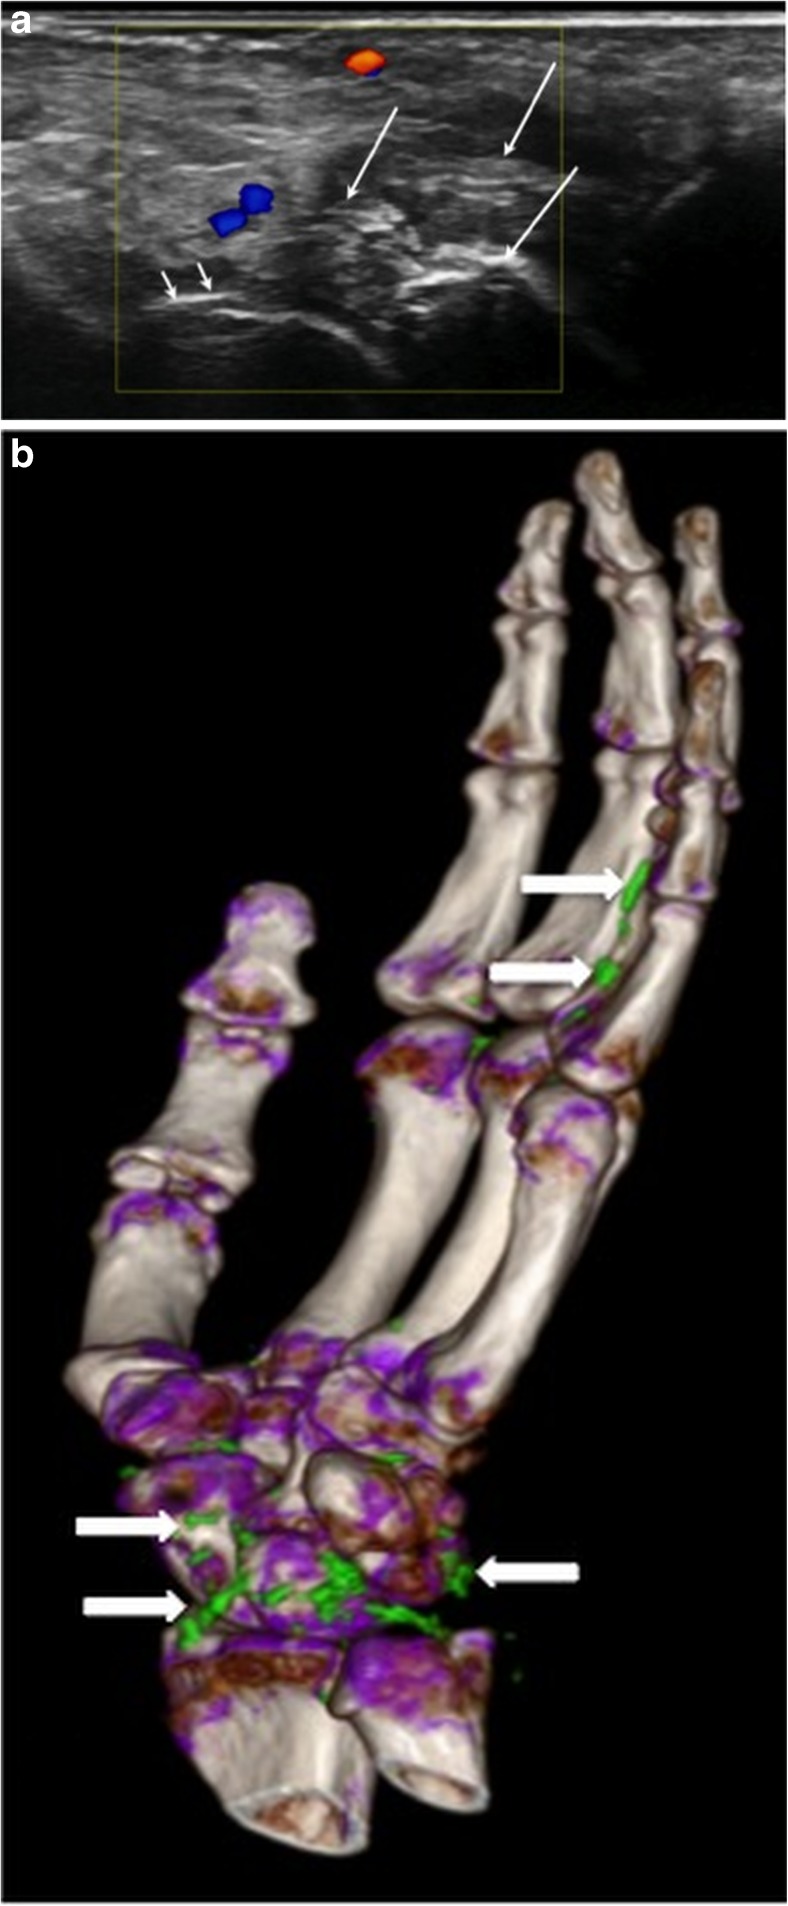

Fig. 4.

Right hand of a 63-year-old male patient. a Longitudinal US scan over the volar wrist showing tophus formation (large arrows) and double contour (small arrows). b DECT 3D volume rendered image of the same hand showing MSU deposits at the wrist and flexor tendons

US has been advanced as an imaging modality of choice for the diagnosis and management of gout [21, 23–25]. In fact, in addition to a positive DECT result, the DCS has been incorporated in ACR/EULAR guidelines 2015 as being the most specific sign for the diagnosis of gouty arthritis [24, 26].

As recorded in our series, only 71/180 patients (39.4%) had a definitive diagnosis of gout with US versus 97/180 patients (53.9%) by DECT. Indeterminate US cases frequently had small deposits, suggesting that cases with less severe findings may be more challenging. Our study shows that osteoarthritis (OA) can be challenging in the US differential diagnosis, as 50.6% of the DECT negative patients were diagnosed to have OA with loose bodies by using coronal reformed CT images, and many of these patients were positive or indeterminate by US. US shows echogenic findings which may be secondary to calcium or MSU deposits, while DECT is capable of discriminating urate from non-urate compounds [22] (Figs. 3 and 4). This limitation of US was confirmed in our study (Table 2) as US showed fewer extra-articular gouty deposits (extensor tendon 22.5%, flexor tendon 15.5%) versus DECT (extensor tendon 30%, flexor tendon 65%). A prospective blinded randomized study by Choi et al. [35] showed a sensitivity of 84% and a specificity of 93% for detection of MSU deposits by DECT, but the most common location of MSU deposits in 20 evaluated patients were in lower extremities, and included only 6 hands/wrists out of 40 joints. The role of DECT has also been shown by Hu et al. [37] reporting a high sensitivity and specificity of 75.2% and 92.7% of DECT for the detection of gouty arthritis in upper and lower extremities. Zhu et al. [38] compared the diagnostic accuracy of DECT and US in various joints in 40 patients, also showing that DECT was superior to US in upper limbs, whereas no difference between the two methods was seen for the lower limbs. Finkenstaedt et al. [11] reported a change in the treatment plan in 23/43 patients with DECT, including 37 hands/wrists in their study.